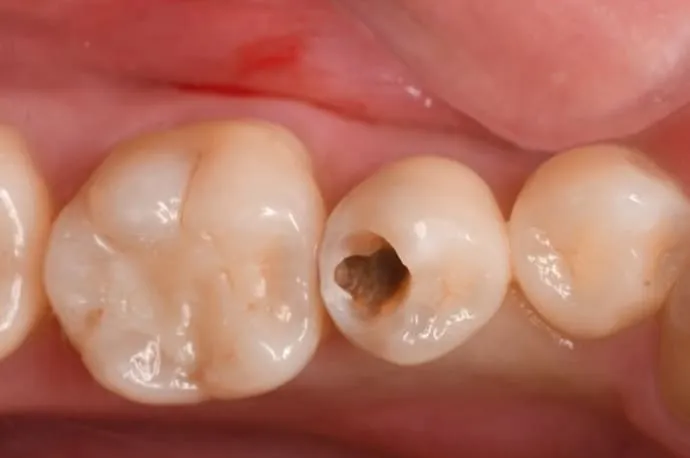

STEP 02

歯の表層を削ると、中は大きな空洞になっています。